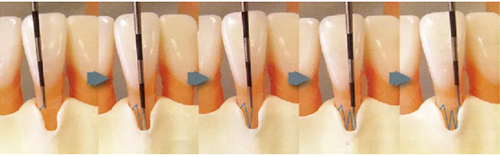

探針在牙周袋內(nèi)的工作方式

~步行式探診~

此時運用的牙周探診技巧稱為“步行式牙周探診法”。

● 步行式牙周探診的操作

牙周探針的工作尖始終與牙體接觸,將工作尖從袋底上提1~2mm的幅度進(jìn)行步行式探診。